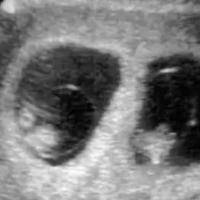

单卵双胎,即由一个受精卵在早期发育过程中自然分裂形成两个独立胚胎所引发的双胞胎妊娠现象,其发生机制复杂且多为随机事件。与双卵双胎不同,单卵双胎不受遗传、人种或生育治疗的显著影响,其发生原因尚未被科学完全阐明,但大量临床观察与研究发现,某些特定人群或生理条件下,女性怀单卵双胎的概率可能存在微弱上升趋势。本文旨在梳理相关因素,为公众提供基于现有医学研究的科普解读。一、这些生理与遗传因素可能带来微弱影响...

双胞胎有单卵和异卵之分,这一点可能很多朋友都清楚,单卵双胞胎是指一开始只有一颗卵子与金子结合,但形成受精卵之后就分裂了,成为两个胎儿。而异卵双胞胎通常是两个卵子与两个精子进行结合的,所以这类双胞胎之间...

双胞胎分为单卵双胎和双卵双胎,一般我们在生活中看到长得很像的双胞胎都是单卵双胎,也就是一个受精卵发育而成的,双胞胎在各方面都很相似。那么,单卵双胎是谁的功劳,做试管有机会怀上单卵双胎吗?单卵双胎是谁的...